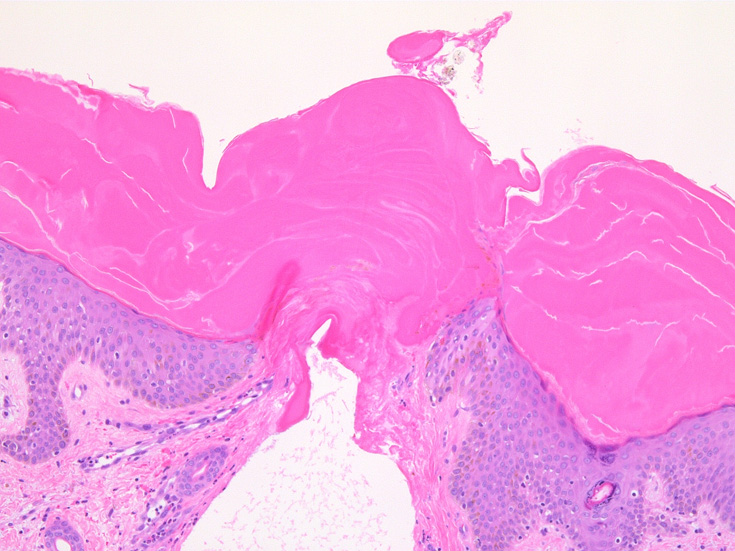

IWT-case02 1歳9ヶ月男児 項部の血豆様腫瘤に気づき来院.

マダニ科マダニ(4属)では触肢と口器は短くなっており,そのために, 吸血後24時間程度経過すると,唾液腺で産生されるセメント様物質を分泌して口下片全体を包みこみ,体を宿主にしっかりと固定する.

(case02の皮膚表面にみられる硝子様の層がそれに相当するようです。)